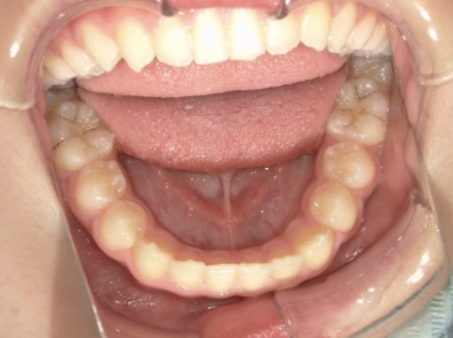

治療中⑨ 中3:14y4m

モノブロック装置で左上八重歯が改善しました

今後、必要によりマルチブラケット法へ移行予定です